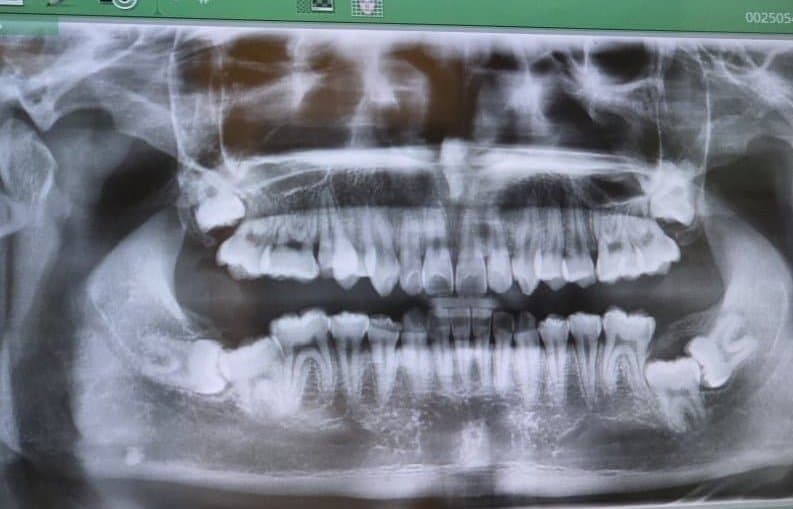

1.

자초지종은 사랑니로 난다긴다 하는 치과 5곳 발품 팔았는데 이건 큰병원 가야한다고 빠꾸먹고 대학병원가서 전신마취하고 매복 사랑니 4개를 한번에 뽑을줄도 몰랐다 지금은 발치 후 2주정도 지나서 밥도 잘먹고 하는데 아직도 턱주가리가 욱신거린다.

발치 전 사진인데

보이는거 처럼 매복도 깊고 옆으로 ㅈ같이 누워있어서 의사쌤도 이따구로 생긴 사랑니는 근래에 처음본다 하셨다

또 굳이 뽑아야겠냐 물어보셨다

그리고 아래 사랑니가 턱뼈 지나는 신경이랑 따악 붙어있어

이거 잘못 건드리면 평생 혀나 입술, 턱쪽에 감각이 마비되서 안면이 장애가 생길 수 있다고 하셨음

순간 나는 전생에 왜적이었나 싶은 생각이 씨게 들었다.